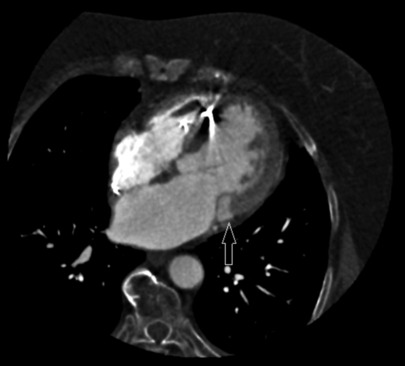

Caseous calcification of the mitral annulus (CCMA) is a rare variant of mitral annular calcification, and a multimodality approach is advised to ensure an accurate diagnosis. We report a case of a patient with CCMA, associated with severe mitral regurgitation. An 82-year-old woman was admitted due to worsening heart failure. Transthoracic echocardiography revealed a fixed, hyperechogenic mass, accompanied by restriction of the posterior mitral leaflet, and subsequent severe mitral regurgitation. Transesophageal echocardiography demonstrated a restricted motion of the posterior mitral leaflet, because of a large, echogenic mass (15 mm × 11 mm), attached to the mitral annulus, vacuolated with a central echolucent aspect, lacking acoustic shadowing. Contrast-enhanced cardiac computed tomography identified a distinct oval mass (18 mm × 11 mm × 19 mm) presenting a central hypodense content and peripheral calcification, strongly suggestive of CCMA. Considering the patient's profile, surgical valvular replacement was considered unsuitable. Therefore, a transcatheter edge-to-edge repair was performed, resulting in mild residual regurgitation.